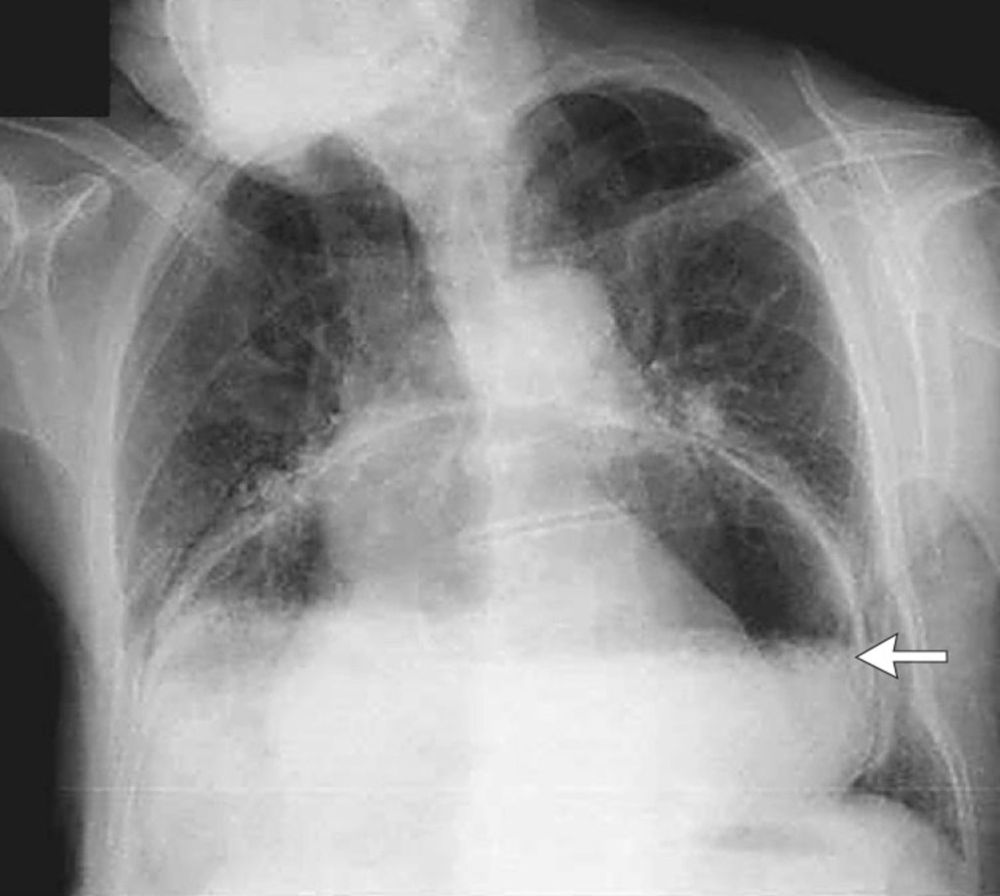

An 81-year-old woman presented with a 1-week history of vomiting.

What is the diagnosis?